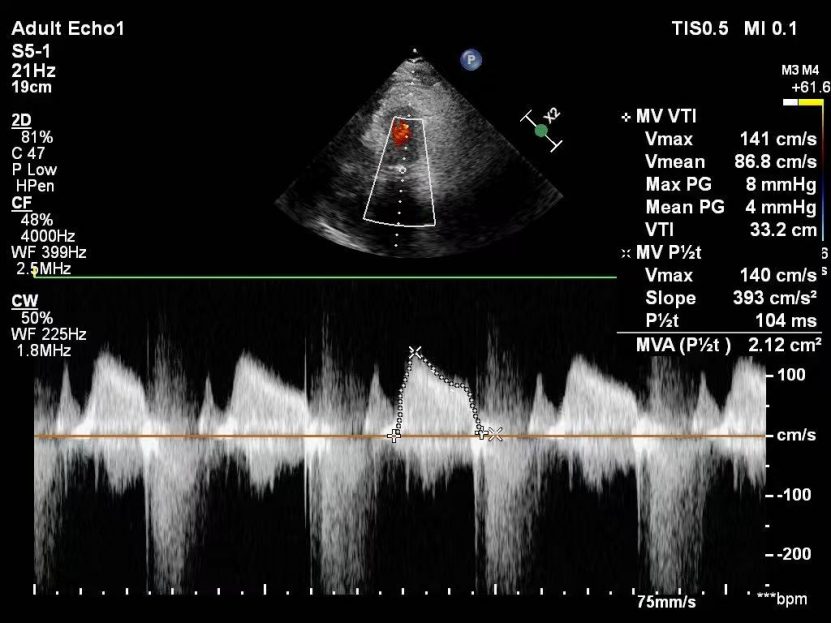

术后复查超声心动图显示:二尖瓣轻度返流,三尖瓣中度返流,二尖瓣可见金属夹回声,启闭正常;各心室大小正常,升主动脉不宽,主瓣回声增强,启闭良好;二尖瓣舒张期峰值流速1.4 m/s,功能面积2.1 cm²,跨瓣平均压差约4 mmHg。

术后即刻反流降为少量,剩余瓣口面积2.57cm²,平均跨瓣压差2mmHg。